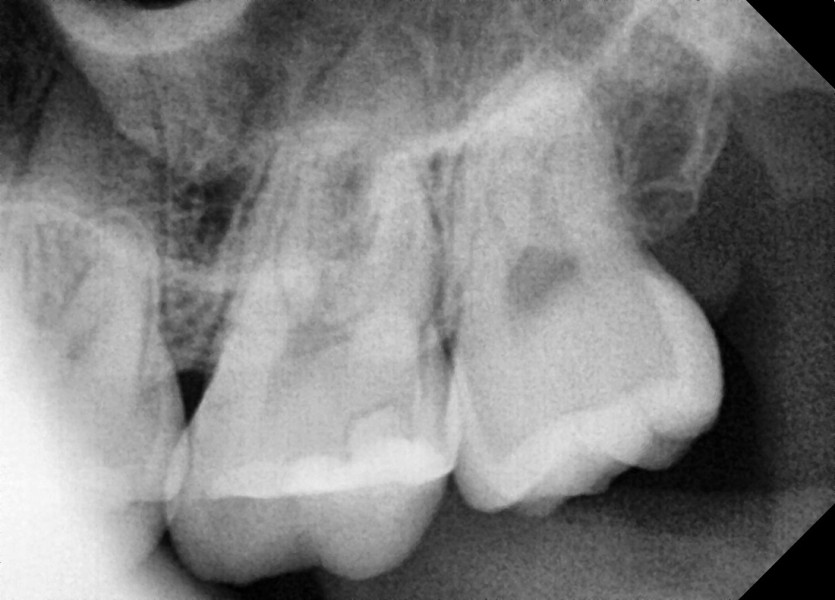

#28,38,48 사랑니 발치

구강 외과 전문의가 당일 발치했습니다.